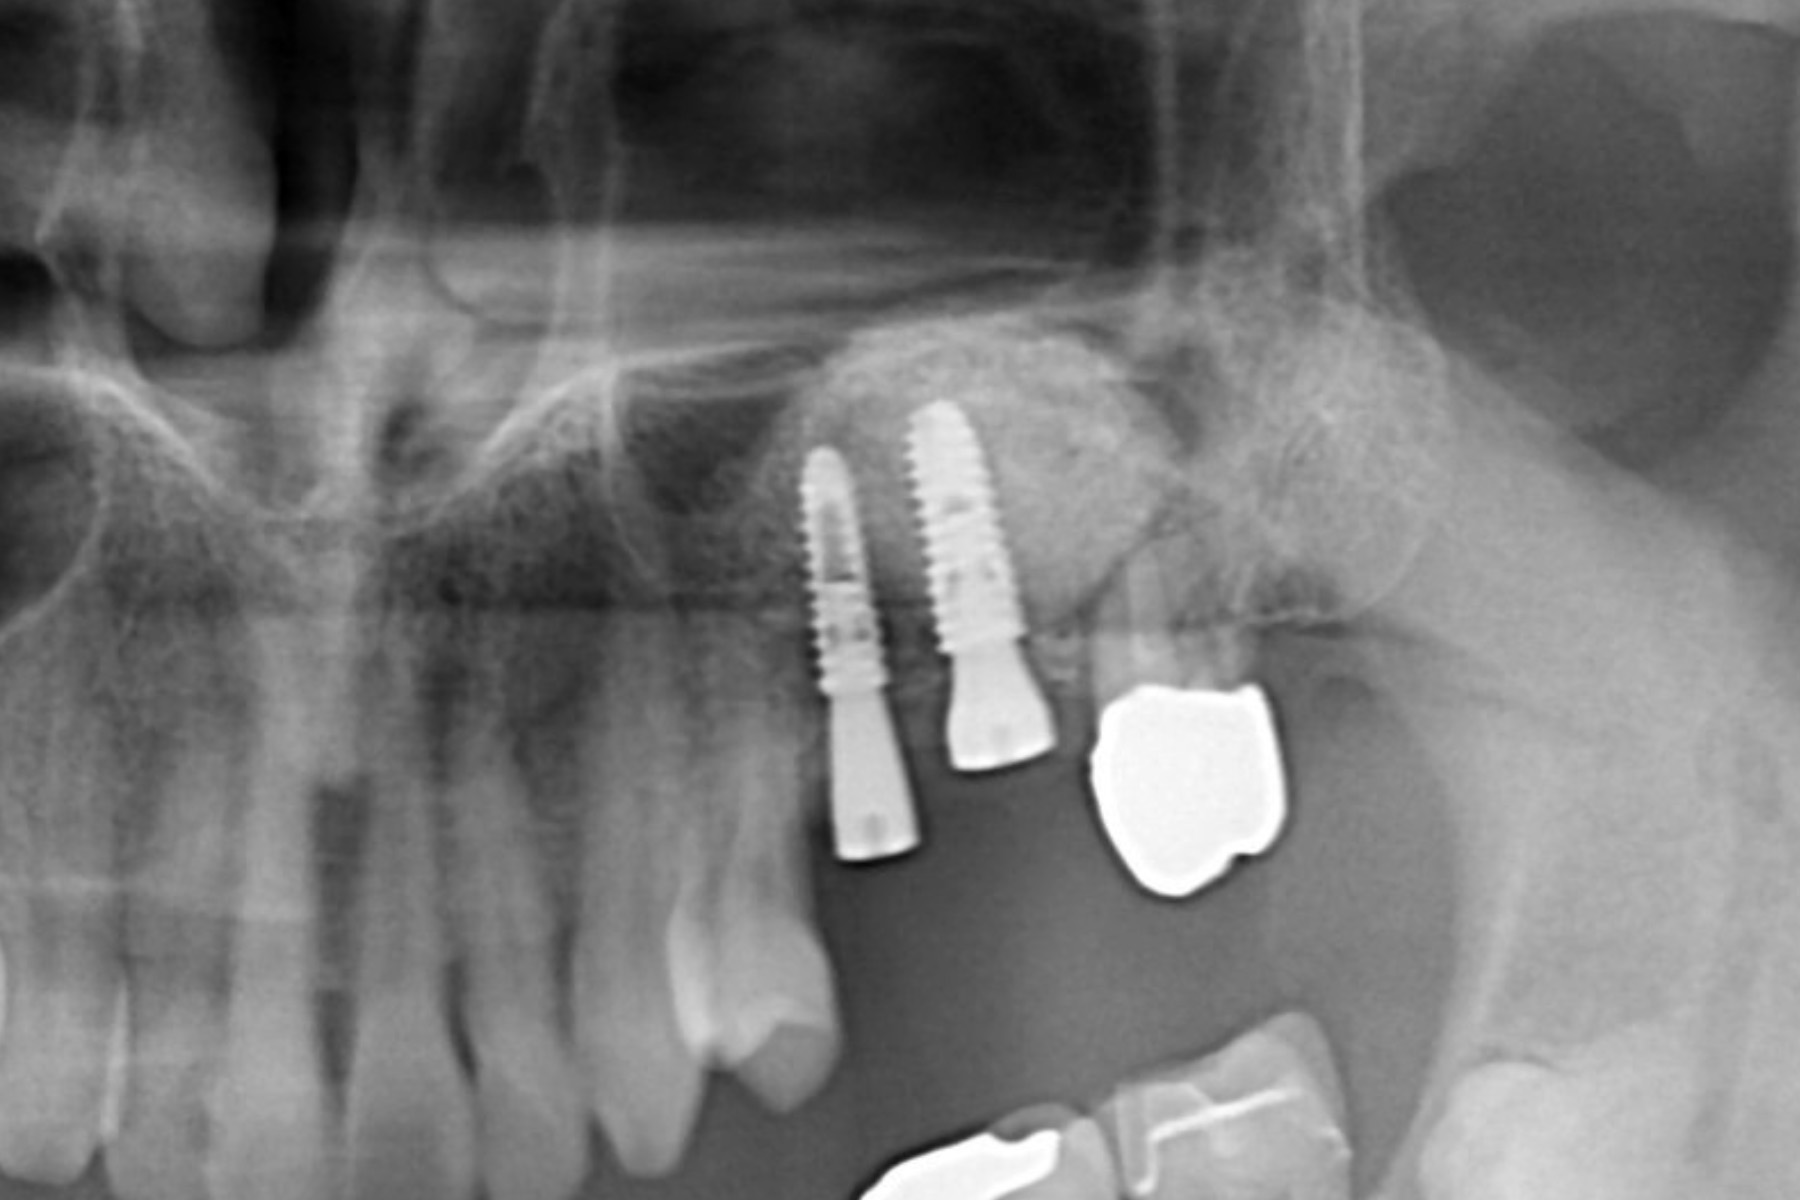

implant-case03-af2